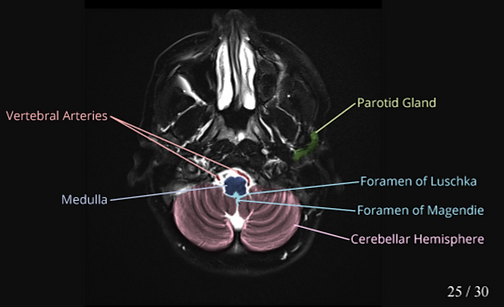

This is the cross-sectional anatomy of brain in MRI. Click the button play to start the video.

This is an axial brain. In this slice, 18 parts of the brain are visualized.